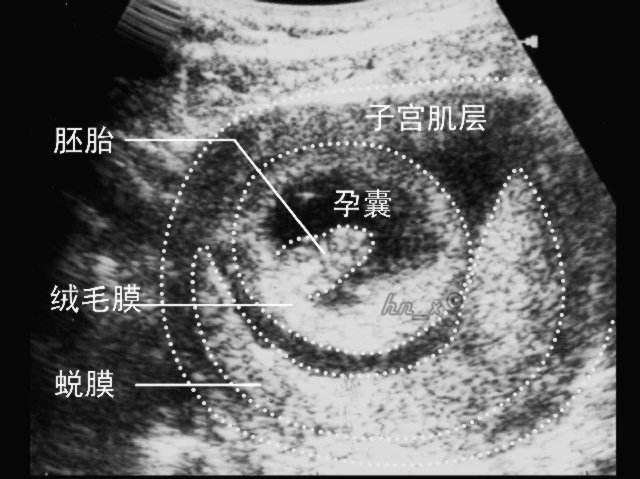

当受精卵着床后,子宫内膜会迅速“蜕膜”,蜕化下来的内膜会把受精卵覆盖并包围在子宫肌肉和内膜之间,受精卵就在这个封闭的囊内慢慢的发育成胎儿,这就是医生常说的“妊娠囊”,也就是我们常说的孕囊。

一般在女性停经5周(大约同房后3周左右)时,正常情况下可以通过阴超,看到明显的孕囊回声,怀孕6-8周时,在孕囊里可以看到卵黄囊、胚芽及胎心搏动,说明胎儿发育的好。